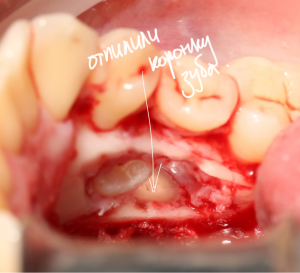

Костная «дверца» на время отделяется и убирается в физраствор, а мы видим следующее:

Это фолликулы и, частично, коронковые части сверхкомплектных зубов.

Теперь аккуратно нам нужно выделить сами зубы:

А вот они! Далее мы руководствуемся главным правилом хирурга-стоматолога:

Поэтому мы, всё также, с помощью ультразвука, отпиливаем коронку одного из зубов: